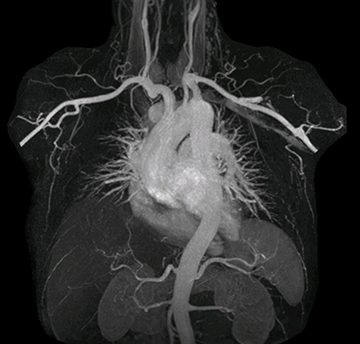

“Before we had Ingenia Ambition, our CE-MRA run-off studies would first acquire a dynamic pre-contrast scan with 20-25-second breath-holds, then inject the contrast, do another acquisition and then subtract the two,” says Avila. “Now, mDIXON XD allows us to complete the study in just one single pass – without need for a pre-exam – which eliminates subtraction artifacts and almost halves the scan time. In addition, mDIXON provides much better background suppression, which really improves vesselto-background contrast. And, thanks to Compressed SENSE, the single breath-hold is not long and we improve image resolution.”

The subtractionless peripheral MR angiography shows improved vessel-to-background contrast and high resolution. Ingenia Ambition 1.5T.

The time saved by Compressed SENSE and mDIXON XD is sometimes used to include additional sequences. An example are peripheral MRA studies, in which Compressed SENSE and mDIXON XD help achieve a 5- to 10-minute reduction in scanning time. This brings the total time down, from the 45 minutes needed with their previous system to about 30 to 35 minutes on Ingenia Ambition, thus providing ample time to include additional sequences.

The images obtained with Ingenia Ambition show large coverage and high uniform signal. More vessels are visible than in a previous exam of the same patient on Achieva. The movies show a higher temporal resolution in the Ambition acquisition than in a previous Achieva 1.5T exam. Both exams use a FOV of 300 mm and voxel height and width of 0.78 mm.

Achieva 1.5T

2:30 min. TE 1 ms, TR 4 ms

Ingenia Ambition

4D Trak XD 1:54 min. TE 1ms, TR 3ms

The team at Miami Cardiac & Vascular Institute also appreciates Ingenia Ambition’s capabilities for fast dynamic CE-MRA. “With 4D TRAK XD, we get much better temporal and spatial resolution. Previously, with the Achieva we needed 6 seconds per dynamic, but now we can shorten that to 2 seconds per dynamic,” Avila says. “As a result, we can see the transition from arterial to venous phase with much higher temporal resolution. This is important, for example, for imaging arteriovenous malformations, which are quite vascular.”

“On our previous system we really had to sacrifice image resolution to get to 5- or 6-second temporal resolution, while now – using 4D TRAK XD on Ambition – we no longer have to sacrifice image quality,” Dr. Peña says.